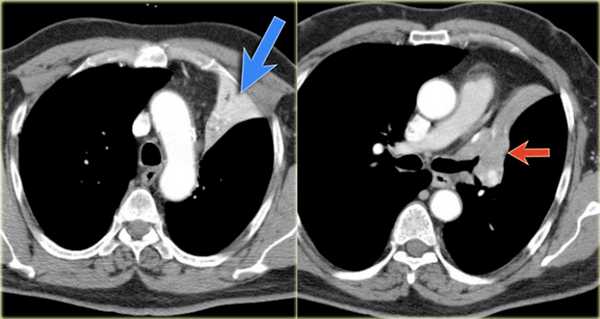

- Минимальное уменьшение объема легкого без подъема левого купола диафрагма.

- В загрудинном пространстве визуализируются изменения высокой плотности, которые спавшейся верхней доли левого легкого.

- Корень левого легкого патологичен, что может соответствовать образованию, обтурирующее просвет бронха.

- Выше перечисленные находки наводят на мысль, что это ателектаз верхней доли левого легкого.

На КТ снимках синей стрелкой указан долевой ателектаз, а красной стрелкой опухоль, которая обтурирует левый верхний долевой бронх (центральный рак легкого.

Ателектаз верхней доли левого легкого с типичным симптомом воздушного серпа (Luftsichel sign — luft(air)+sichel(sickle)), обусловленный гипервентиляцией верхнего сегмента нижней доли левого легкого на фоне коллапса верхний доли левого легкого. Гипервентилируемый

сегмент визуализируется на прямой рентгенограмме от дуги аорты до апикальной части легкого.